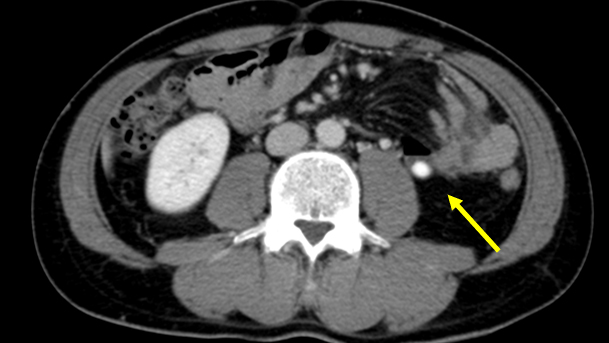

No. 154 症例4:30歳代男性

【画像所見まとめ】

• 脾多発腫瘤、脾門部多発リンパ節腫大

平均年齢は29歳、臨床症状は発熱(90%)、腹痛(67%)、体重減少(50%)。 症状の持続期間は、膿瘍が発見されるまで平均4.7ヵ月。 脾臓が最も多く(71.8%)、リンパ節(50.7%)、皮膚(29.5%)、肝臓(28.1%)、肺(22.5%)。まれな部位は脳、生殖器、腎、頸部、筋、乳房。